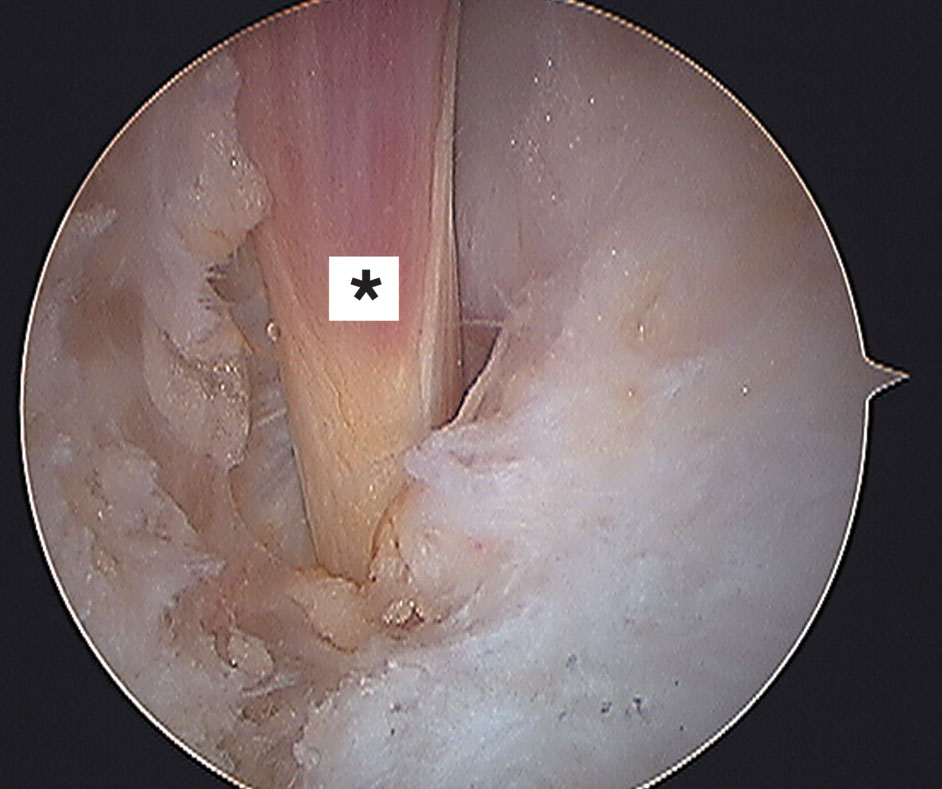

Se realiza inmediatamente medial al tendón de Aquiles y a la misma altura del posterolateral. Al igual que el portal posterolateral sólo se incide piel y con una pinza roma se toca en forma perpendicular la camisa del artroscopía, ya en el portal posterolateral. Las estructura en riesgo en este portal es el paquete vasculonervioso tibial posterior que se encuentra adelante del tendón flexor largo del hallux (Fig 11). Luego se introduce la punta del sistema motorizado a utilizar, se recomienda de pequeño calibre (3 mm) y se desliza tocando la camisa del artroscopio hasta alcanzar la parte posterior de tobillo. Con precaución se resecan tejidos blandos: grasa periarticular y ligamento de Rouviére y Canela, y se busca el tendón del flexor largo del hallux (Fig. 12) que sería en el tobillo posterior la estructura a reconocer para trabajar sin riesgo de lesionar el paquete vasculo nervioso tibial posterior que como mencionamos

se encuentra por delante de este tendón. Es útil movilizar el hallux para ver como excursiona el tendón con su vientre muscular y visualizarlo más rápido y mejor. Trabajos de estudios de investigación anatómicos como los de Sitler y Lijoi sugieren que los portales posterolateral y posteromedial cercanos al tendón de Aquiles y proximales al maléolo peróneo son seguros para acceder al tobillo posterior (18, 19, 20, 21, 22, 23).

Figura 12: Vista artroscópica del flexor largo del hallux.